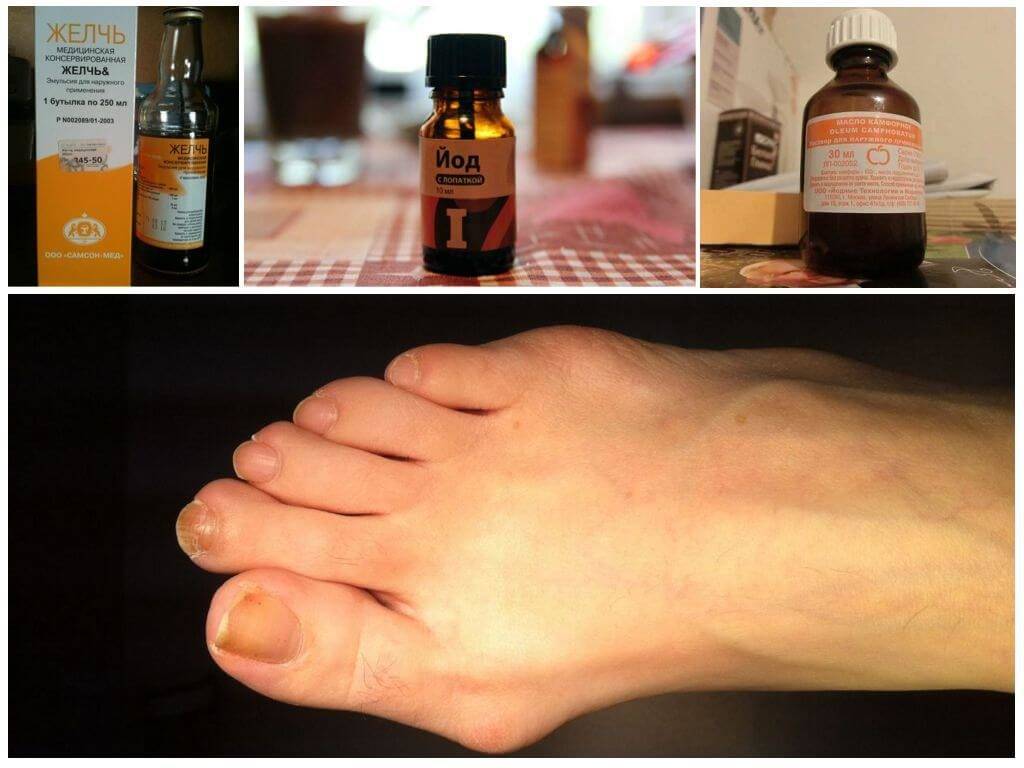

Регулярно делайте теплые ванночки для ног с добавлением морской соли или эфирных масел для снятия воспаления.

Применяйте компрессы с лечебными мазями или гелями для снятия отечности и воспаления.